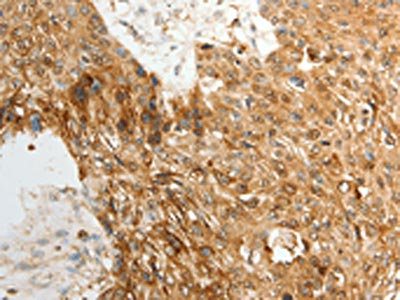

The image on the left is immunohistochemistry of paraffin-embedded Human esophagus cancer tissue using CSB-PA012753(TENM3 Antibody) at dilution 1/50, on the right is treated with synthetic peptide. (Original magnification: ×200)

The image on the left is immunohistochemistry of paraffin-embedded Human ovarian cancer tissue using CSB-PA012753(TENM3 Antibody) at dilution 1/50, on the right is treated with synthetic peptide. (Original magnification: ×200)